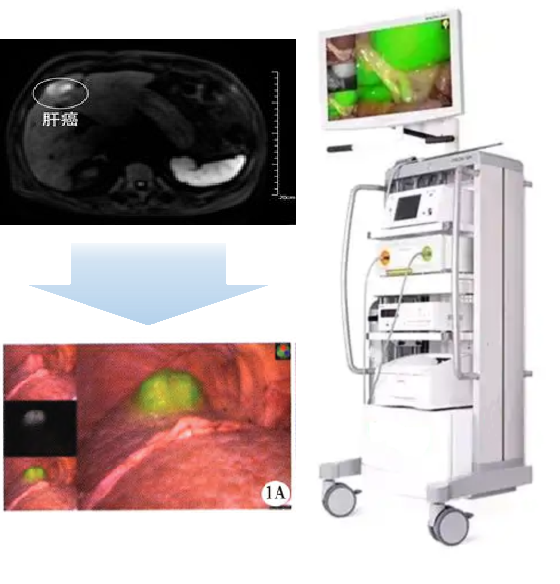

(二)适应症:本品拟用于原发性肝癌患者的术前诊断及术中导航。

PL002是浙江3044am永利官网药业有限公司研发的荧光/磁共振双模态造影剂,开发荧光/磁共振双模态造影剂成为提高原发性肝癌手术效率的有效方案。双模态造影剂的荧光成像能力可用于肝癌术中荧光导航,而磁共振增强能力可用于在术前判断肝脏代谢能力,推测肿瘤及肝脏对造影剂的摄取情况,提高肿瘤诊断精度,降低术前规划难度。

PL002相较于吲哚菁绿具有明显优势。目前吲哚菁绿在临床使用中存在给药到手术时间不确定的问题,可能造成病灶与正常组织对比度不足,影响术中的病灶的判断,PL002采用独特的钆络合物与荧光分子共价键结合的分子结构设计,这种设计能够让医生在术前通过磁共振成像确定造影剂在病灶中的聚集情况,进而针对患者个体情况来对手术时间进行规划。同时,由于PL002体内更为稳定,在荷瘤小鼠模型中同等条件下荧光成像效果维持时间长于现有荧光造影剂,也保证了其在临床应用中具有更宽的手术窗口。